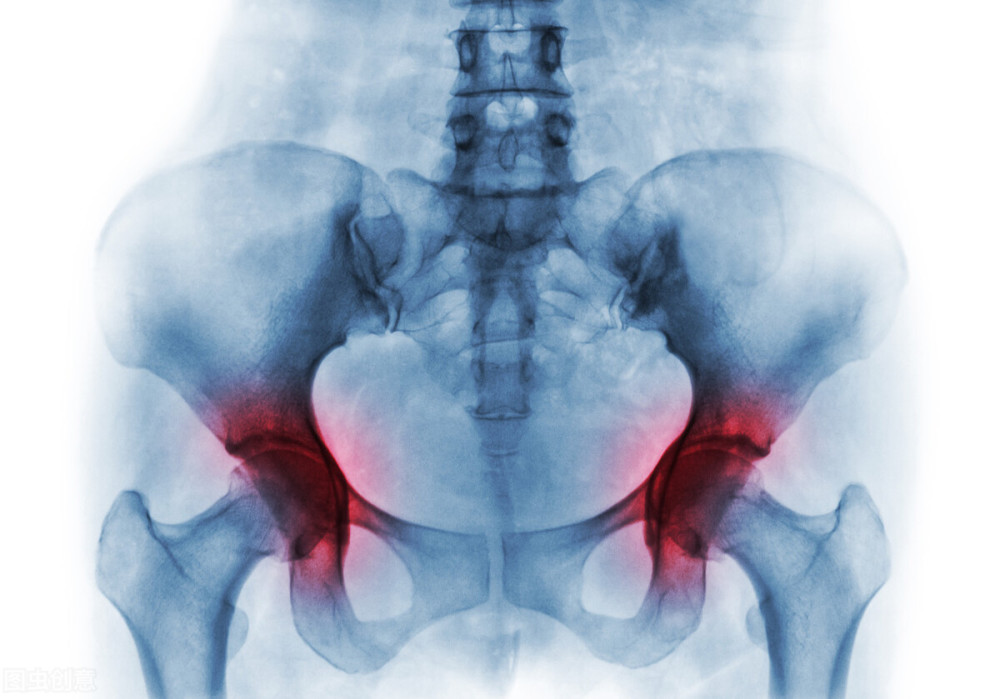

股骨头坏死有哪些症状?

患上股骨头坏死后,患者主要的症状有臀部、腹股沟酸疼、髋关节疼痛,

在负重或者运动后这种症状会明显加重,如不妥善治疗的话,可导致髋关节功能障碍甚至终身残疾。

早期的股骨头坏死怎么治疗?

目前尚无一种方法能治愈不同类型、不同分期及不同坏死体积的股骨头坏死。制定合理的治疗方案应综合考虑分期、坏死体积、关节功能以及患者年龄、职业等。

1.保护性负重

学术界对于该方法能否减少股骨头塌陷仍有争论。使用双拐可有效减少疼痛,但不提倡使用轮椅。

2.药物治疗

通过往髋关节的腔内及时注射臭氧和阿尔法复合药物,并为患者开一些能够促进骨骼愈合、生长的药物,来恢复病患处的血运,进而加速坏死骨恢复。

3.物理治疗

包括体外震波、高频电场、高压氧、磁疗等,对缓解疼痛、促进骨修复有益。

4.手术治疗

人工关节置换术对治疗股骨头骨坏死效果较好,但由于术后出现一些并发症:如感染,股骨上端劈裂,假体移动或下沉等,而且一旦手术失败,再无其他手术可以补救,所以对该手术的适应证应从严掌握。